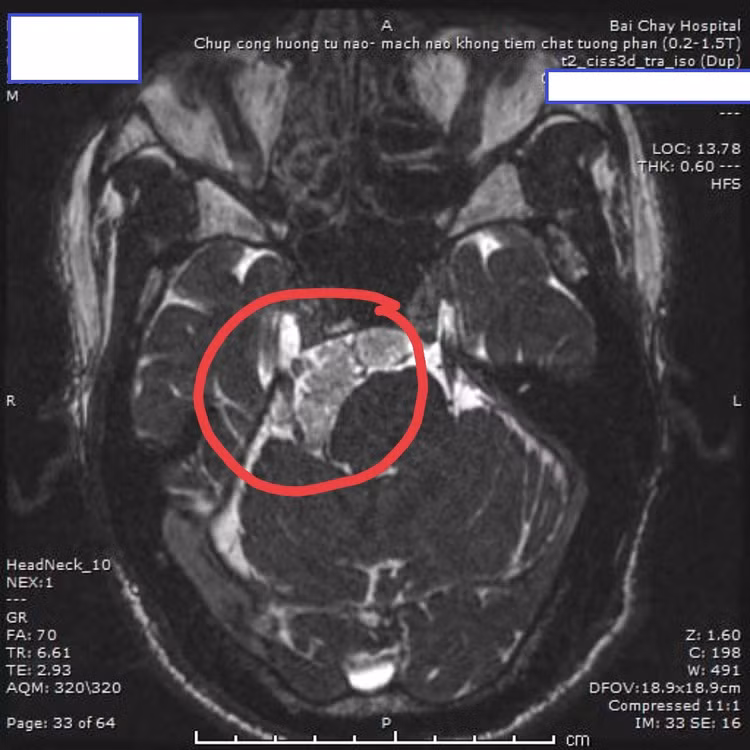

Bệnh nhân Đỗ.V.C (1967, Quảng Ninh) bị đau đầu, đau nửa mặt nhánh V, I, II, III, chóng mặt trong khoảng 6 tháng, điều trị nội khoa không thuyên giảm. Khám lâm sàng, thực hiện các xét nghiệm chuyên sâu và chụp cộng hưởng tử cho thấy: Có khối ngấm thuốc kích thước 5x2cm kéo dài từ nền sọ vùng trên yên tới vị trí góc cầu tiểu não bên phải, đè đẩy vào cầu não và cuống tiểu não phải, có xung đột mạch máu và dây thần kinh số V phải. Các bác sĩ đã hội chẩn chỉ định phương pháp phẫu thuật vi phẫu thuật cắt u và giải ép thần kinh V có nội soi hỗ trợ.

Vị trí u tại vùng góc cầu tiểu não trên phim MRI